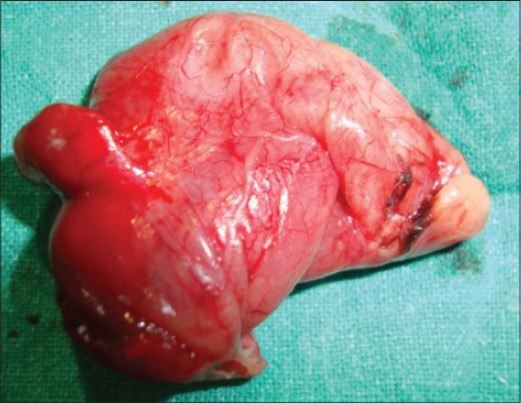

Gross examination of the excised cyst reveals a smooth surface lining of uniform thickness without papillary projections (Courtesy Dr. V. Penopoulos)